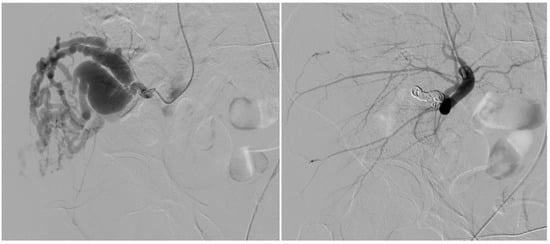

Embolic regimens comprised a combination of coils and ethylene vinyl alcohol copolymer (EVOH) in four patients (44%), coils alone in three (33%), EVOH alone in one (11%) (Figure 1), and EVOH plus polyvinyl alcohol particles in one (11%).

Figure 1. A 17-year-old patient. Type I AVM from the collateral branch of the peroneal artery. The left image shows an angiographic examination performed pre-procedure. The right image shows post-embolization angiography performed with a Progreat microcatheter and injecting EVOH particles alone.